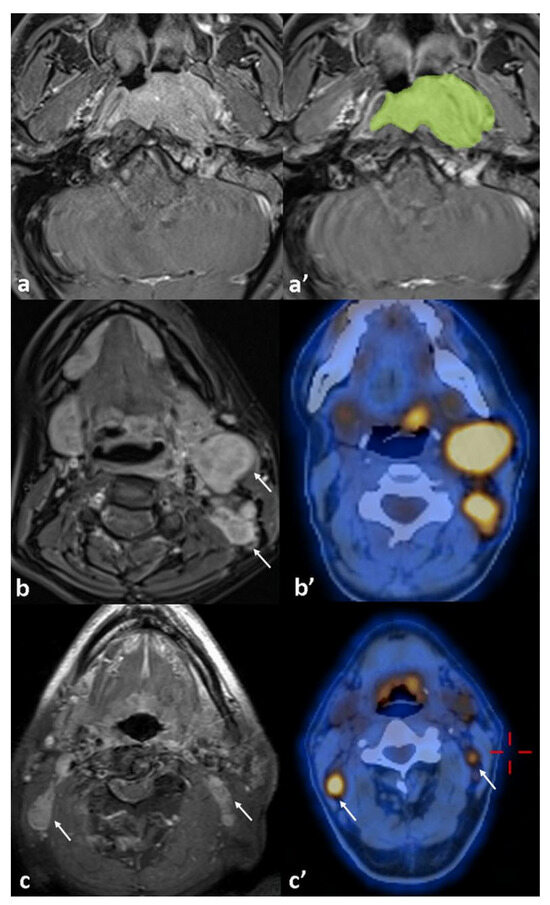

| 18FDG-PET/CT (PT) | 0.915 0.757 | ||

| MTV | 21.7 (±3.1)/42.2 (±11) | 0.049 * | |

| TLG | 164.4 (±27)/394.2 (±121) | 0.045 * | |

| SUV-max | 14.9 (±1.1)/15.9 (±2) | 0.328 | |

| SUV-mean | 6.8 (±0.4)/7.6 (0.7) | 0.195 | |

| SUV-peak | 12.2 (±0.9)/13.4 (±2) | 0.281 | |

| 18FDG-PET/CT (LN) | |||

| MTV | 19.7 (±4.8)/16.3 (±3.9) | 0.295 | |

| TLG | 149.4 (±38.8)/139.6 (±42.5) | 0.445 | |

| SUV-max | 12 (±1.1)/13.5 (±1.9) | 0.261 | |

| SUV-mean | 5.9 (±0.5)/6.4 (±0.9) | 0.314 | |

| SUV-peak | 9.4 (±1)/10.9 (±1.8) | 0.240 |